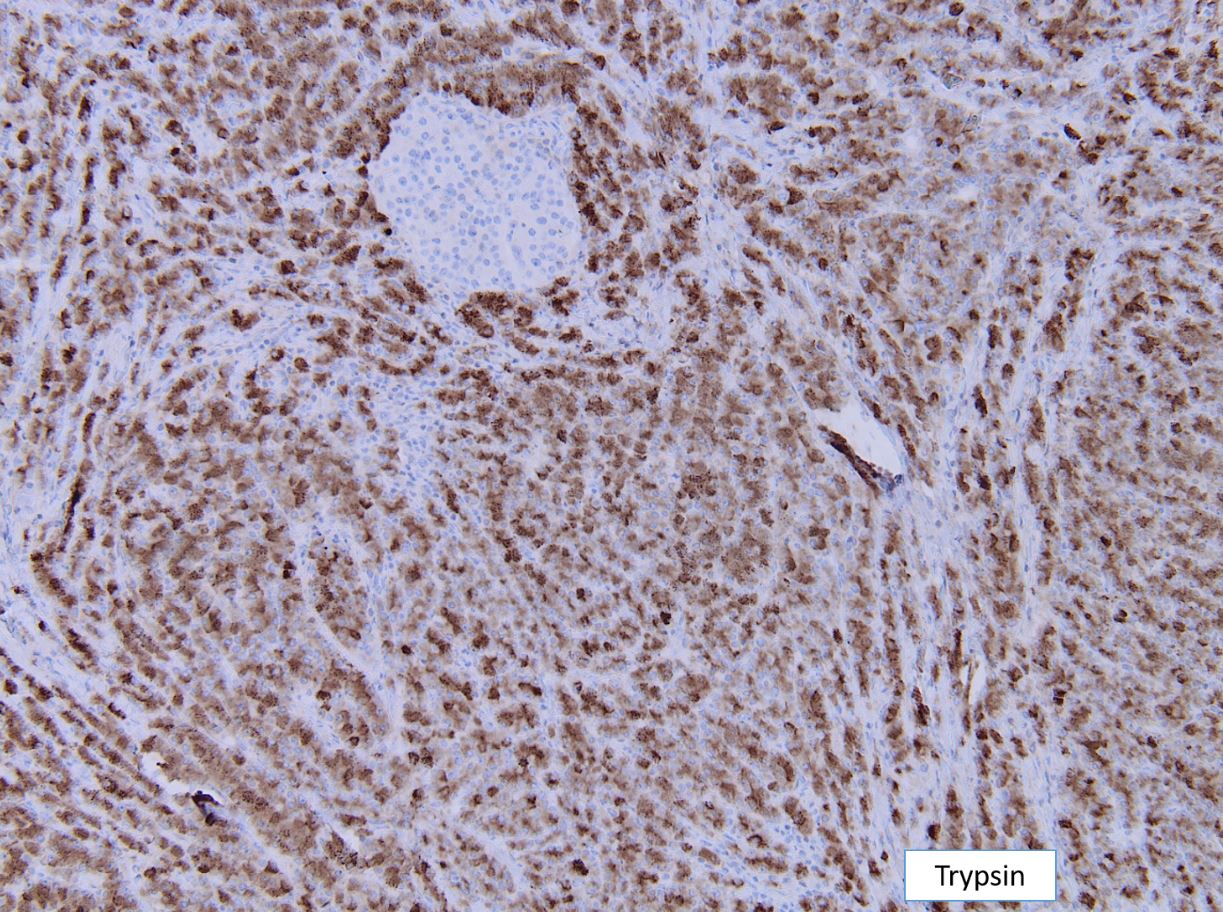

“C.” Trypsin (+), BCL10 (+)

The tumor is solid and cellular with the individual cells displaying abundant granular cytoplasm and round monotonous nuclei with prominent nucleoli, configured in a vague acinar formation. These features are consistent with an acinar cell carcinoma, therefore positive staining for trypsin and BCL10 are expected (figures).

The main differential diagnosis in this case is a well differentiated neuroendocrine tumor. However, a stain for synaptophysin stain is negative, with an islet serving as an internal control. This finding rules out a neuroendocrine tumor, therefore chromogranin would also likely be negative. Acinar cell carcinoma can sometimes have weak staining for neuroendocrine markers, however the KI67 index should be high in acinar cell carcinoma. Pancreatoblastoma is also an important differential diagnosis for acinar cell carcinoma. The background of pancreatoblastoma is often that of an acinar pattern with corresponding trypsin positivity. However, pancreatoblastoma will contain squamoid nests that show nuclear staining for beta-catenin. Solid pseudopapillary neoplasm (SPN) should also be considered as a differential, as it is a solid and cellular neoplasm with bland cytology. However, acinar cell carcinoma lacks the distinctive small capillaries and pseudo papillae formation seen in SPN. SPN will also have characteristic nuclear beta catenin staining.